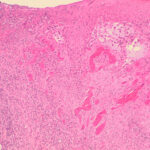

Histopathology . Pyoderma gangrenosum exhibits a dichotomous tissue reaction, showing central necrotizing suppurative inflammation, usually with ulceration, and a peripheral lymphocytic vascular reaction comprising perivascular and intramural lymphocytic infiltrates, usually without fibrin deposition or mural necrosis . Transitional areas show neutrophils in a loose cuff around the angiocentric lymphocytic infiltrates, defining a mixed lymphocytic and neutrophilic vascular reaction termed a Sweet’s-Iike vascular reaction . Bullous lesions may also demonstrate a Sweet’s-like vascular reaction with perivascular disintegrating neutrophilic infiltrates and hemorrhage without mural necrosis or luminal fibrin deposition. At variance with Sweet’s syndrome is destruction of the connective tissue framework with resultant tissue pathergy . Although a leukocytoclastic vasculitis may be observed in areas of maximal tissue pathology, pyoderma gangrenosum does not reflect a primary vasculitis . In some cases a necrotizing pustular follicular reaction may be the central nidus of the lesion, particularly in the vesicular pustular variant associated with ulcerative colitis or hepatobiliary disease. In the superficial granulomatous variant, florid pseudoepitheliomatous hyperplasia may be observed along with the intraepithelial and superficial dermal suppurative granulomatous inflammation with admixed plasma cells and eosinophils . Gases of pyoderma gangrenosum associated with Grohn’s disease may have areas of granulomatous inflammation . |